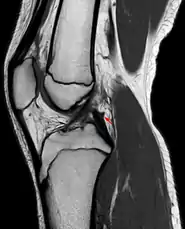

Posterior meniscofemoral ligament on MRI, sagittal

Posterior meniscofemoral ligament (Wrisberg) behind the posterior horn of the lateral meniscus close to its insertion. Sometimes wrongly interpreted as a meniscal tear.